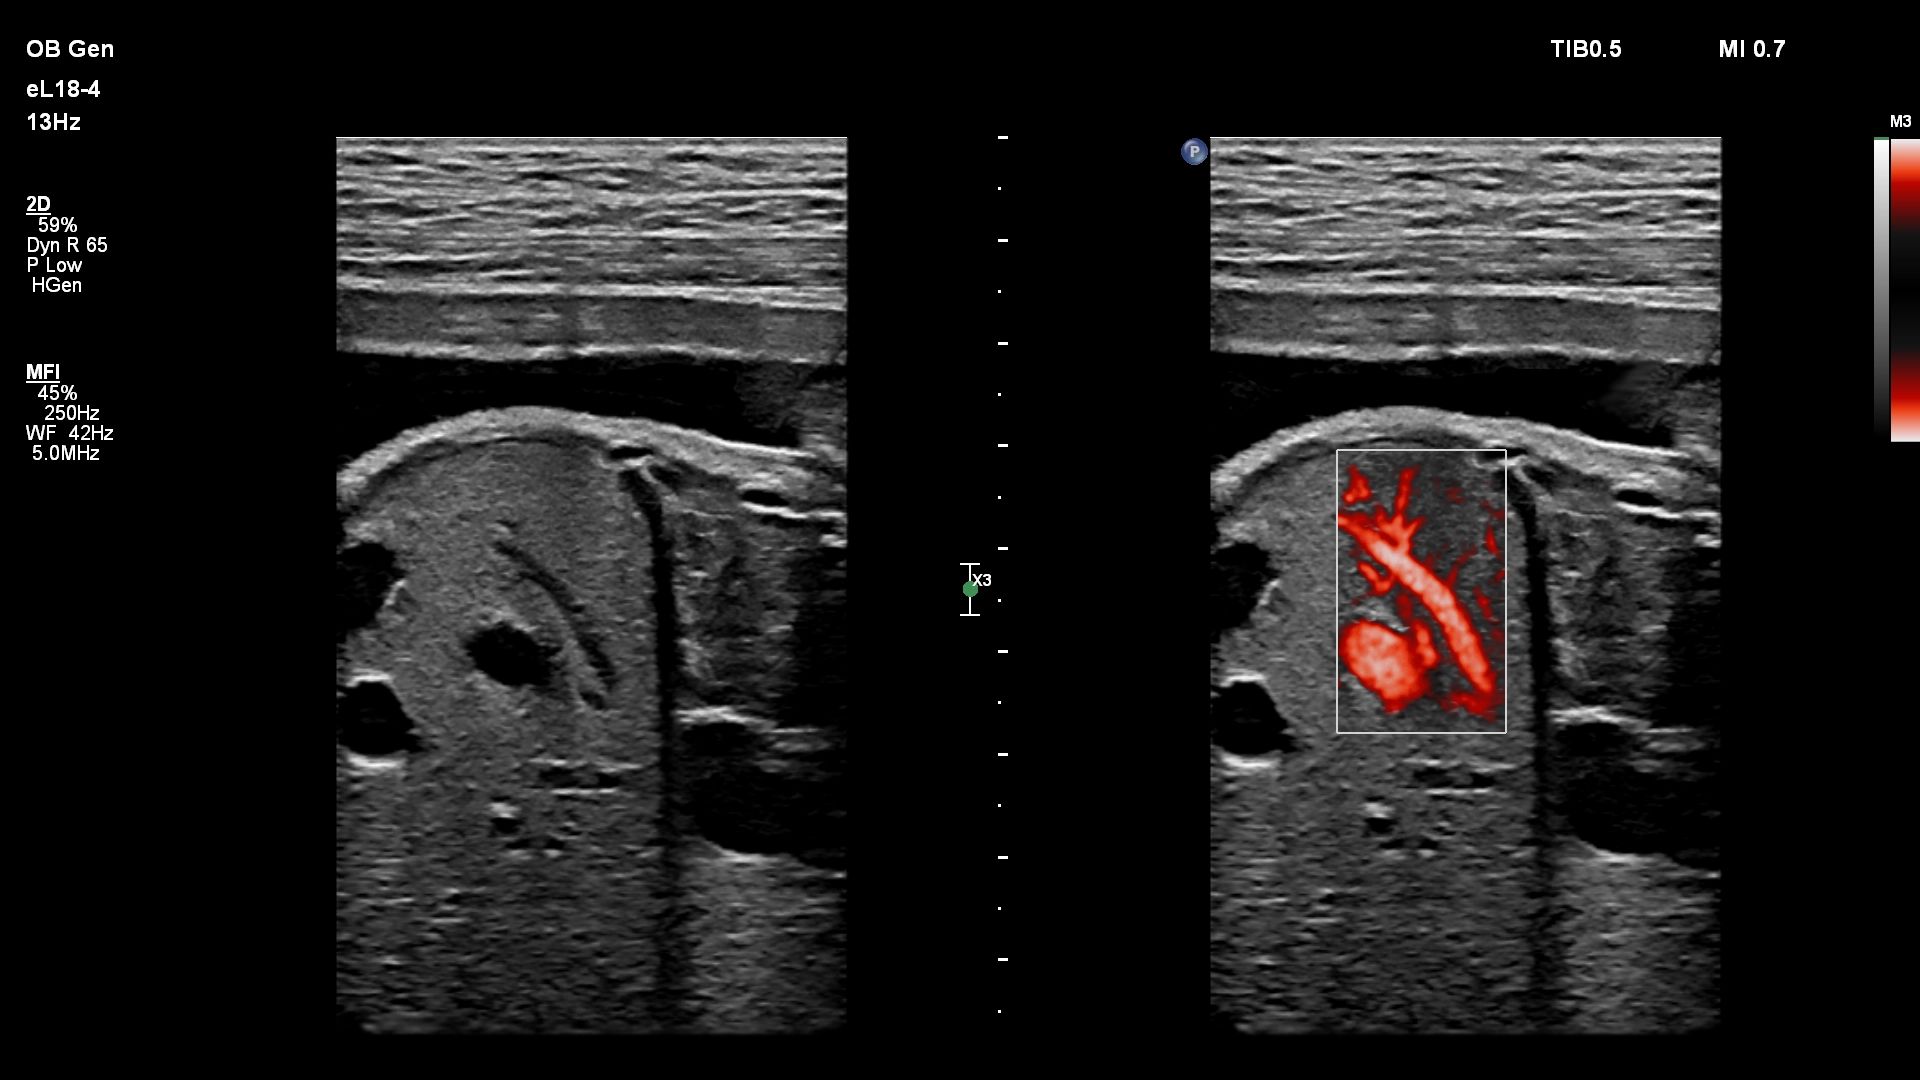

- Сосудистые исследования

Функции для исследования сосудов

- VPQ (Vascular Plaque Quantification) - функция автоматического количественного анализа атеросклеротических бляшек в сонной артерии в режиме 3D. Функция автоматически вычисляет количество бляшек, площадь просвета сосуда и идеально подходит для полноценного анализа состава атеросклеротических бляшек

- Auto Doppler - автоматическая настройка импульсно-волнового допплера и ЦДК

- Micro Flow Imaging - возможность визуализации сосудов с низкой скоростью кровотока для точного анализа и оценки перфузии небольших сосудов

- Энергетический доплер CPA

- Функция Auto Doppler для исследования сосудов

- Визуализация сосудов MVI